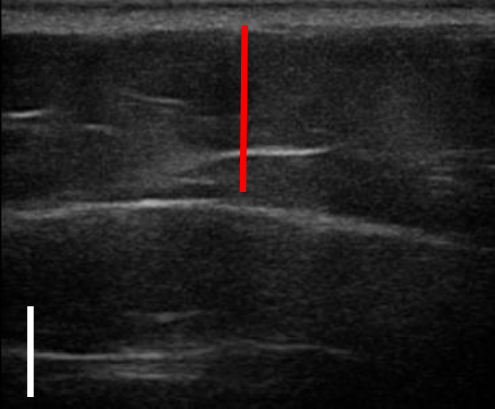

트루스컬프iD 시술 전 / 12주 후 초음파 사진 비교

트루스컬프 아이디 시술 전, 12주 후 초음파를 비교한 사진입니다.

앞서 보았던 뱃살 사례보다 눈에 띄는 변화는 없었으나 실제로 감소한 지방량이 상당했는데요. 시술 전과 비교했을 때 약 31% 정도 지방이 감소했습니다.

뱃살, 옆구리살이 너무 많은 경우 실제 눈에 보이는 것보다 내부에 쌓여있는 지방이 두터운 경우가 많아 시술을 해도 큰 변화를 보이지 않는 경우가 많은데요. 실제로 시술 후 큰 변화가 없어 실망하는 분들도 많지만 위와 같이 초음파 검사를 통해 속을 들여다보면 상당 부분 지방이 감소한 것을 확인할 수 있습니다.